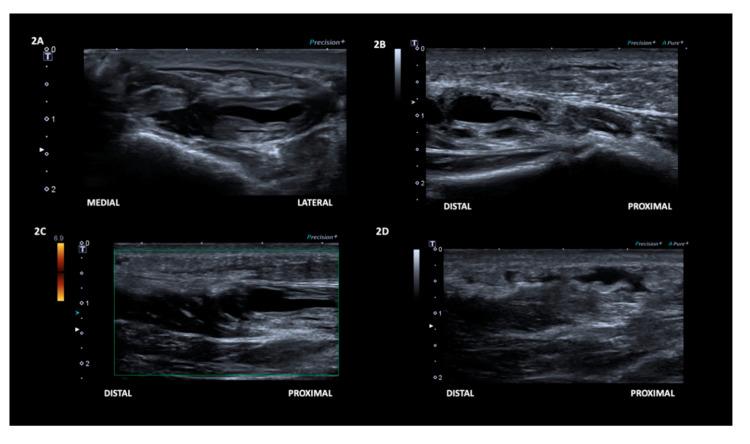

In the current study, we present a case of an intramuscular ganglion cyst in the flexor hallucis brevis muscle (FHB) that arose secondary to a muscle tear. Through this study, we propose a possible aetiology for the development of intramuscular ganglionic cysts. A 50-year-old woman presented with acute pain and swelling over the right mid-plantar area after prolonged kneeling for scrubbing floors. Ultrasonography examination performed at 5 days after the onset of symptoms revealed a partial tear of the right FHB. Follow-up evaluations were conducted, with magnetic resonance imaging and ultrasonography, at 24 and 54 days after symptom onset. MRI revealed a ganglion cyst in the mid-portion of the FHB without connection to the adjacent joint capsule or tendon sheath. On the ultrasonography examination at 45 days after onset, at the same location where a tear was seen on the initial examination, an anechoic defect in the mid-portion of the FHB was observed, compatible with a ganglion cyst. Given the favourable natural evolution, no aspiration or surgery were performed. The patient was discharged with minimal symptoms. The results suggest that the intramuscular ganglion cyst can develop following a muscle tear.

在本研究中,我们报告了一例发生于拇短屈肌(FHB)的肌内腱鞘囊肿病例,该囊肿继发于肌肉撕裂。通过本研究,我们提出了肌内腱鞘囊肿形成的一种可能病因。一名50岁女性在长时间跪着擦地板后,右足底中部区域出现急性疼痛和肿胀。症状出现5天后进行的超声检查显示右FHB部分撕裂。在症状出现后24天和54天,通过磁共振成像和超声进行了随访评估。MRI显示FHB中部有一个腱鞘囊肿,与相邻的关节囊或腱鞘无连接。在发病后45天的超声检查中,在初次检查发现撕裂的同一位置,观察到FHB中部有一个无回声缺损,符合腱鞘囊肿表现。鉴于其自然转归良好,未进行抽吸或手术治疗。患者出院时症状轻微。结果表明,肌内腱鞘囊肿可在肌肉撕裂后形成。